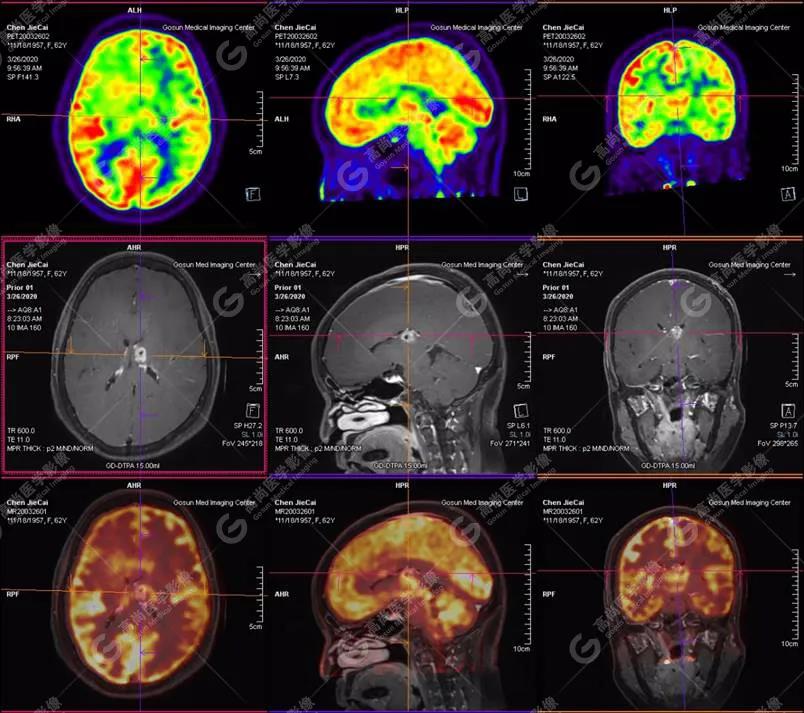

【廣東高尚醫(yī)學影像】多模態(tài)影像|顱內(nèi)淋巴瘤PET-MR融合顯像1例

左側(cè)顳葉、頂葉、左側(cè)基底節(jié)區(qū)及胼胝體部多發(fā)結(jié)節(jié)狀高代謝病灶,部分合并囊變、出血,MR平掃+增強示不均勻輕、中度強化,綜合考慮為顱內(nèi)原發(fā)惡性腫瘤,以淋巴瘤可能性大

腫瘤可發(fā)生于顱內(nèi)任何部位,多見于大腦深部和中線結(jié)構(gòu),好發(fā)于基底神經(jīng)節(jié)、胼胝體、腦室周圍白質(zhì)和小腦蚓部。本病臨床表現(xiàn)無特異性,依腫瘤所在部位而異,多以顱內(nèi)高壓和局灶性體征首發(fā)。本病病程短,進展快,預后差,其生長特點為多中心生長,即使單發(fā)病灶也是多中心生長病灶的融合,導致與腦轉(zhuǎn)移病灶診斷上鑒別困難。

淋巴瘤病變多位于中線兩旁的深部腦實質(zhì)、側(cè)腦室周圍及腦表面,甚少累及腦膜和顱骨,幕上多于幕下,呈分葉狀或握拳狀,水腫及占位效應較輕,部分病灶內(nèi)可見囊變、出血及其邊緣的硬環(huán)征、尖角征、臍凹征,增強掃描呈現(xiàn)的“臍凹征或者“握拳征”是淋巴瘤較為特征性的一個表現(xiàn)。

18F-FDG PET PET顯像中呈明顯高代謝病灶。

顱內(nèi)惡性淋巴瘤對18F-FDG的攝取率很高,一般SUV在5~10以上,18F-FDG PET顯像中攝取明顯高于正常腦皮層,因此具有特征性。

PET/CT-MR檢查是原發(fā)顱內(nèi)惡性淋巴瘤的重要檢查方法,能有效提高診斷正確率;在早期發(fā)現(xiàn)、準確分期、放化療后檢測具有極重要的作用。